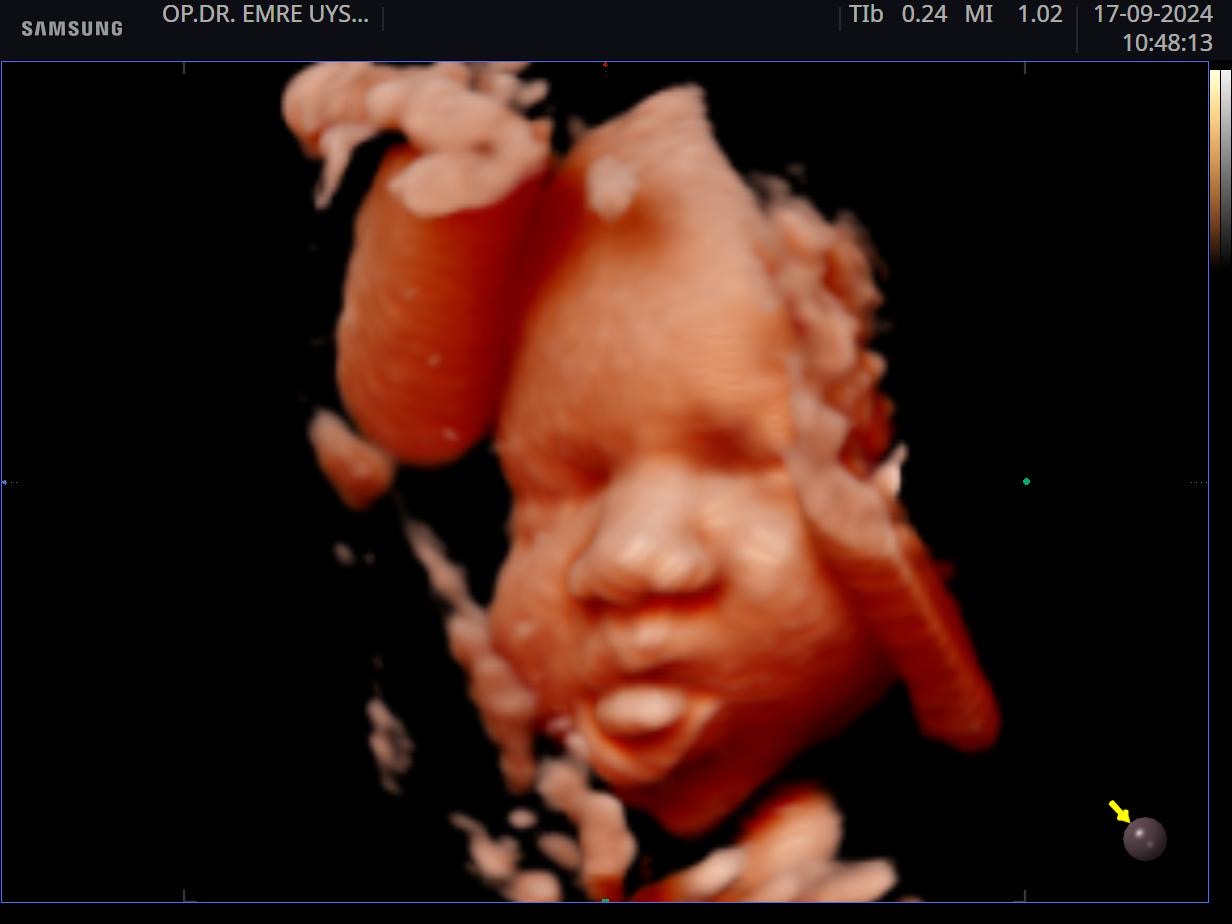

Her kadının hayatında önemli dönüm noktaları vardır. Hiç şüphesizki hamilelik süreci ve doğum bunlardan en kıymetlisidir. Biz de bu değerin farkındayız ve 15 yılı aşan tecrübemiz ile minik mucizenize sağlıkla kavuşma yolculuğunda sizin yanınızdayız. 4d ultrason ile bebeğinizin sağlığını yakından takip ederken, klinik takibimiz ile de süreci eğlenceli ve sağlıklı bir şekilde geçirmeniz için elimizden gelenin en iyisini yapıyor olacağız. Yaşasın Hamilesiniz!